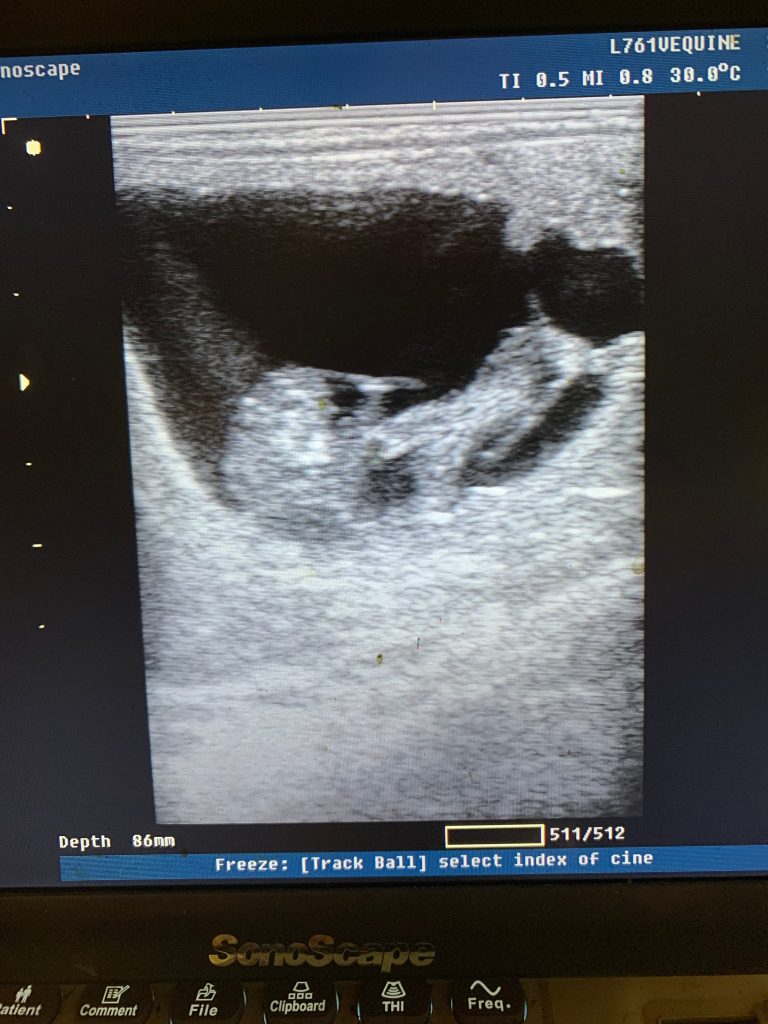

Dia Dina had a foal with De Viano

Dia Dina is in fol with De Viano and we expect her to foaling at 1/6-23